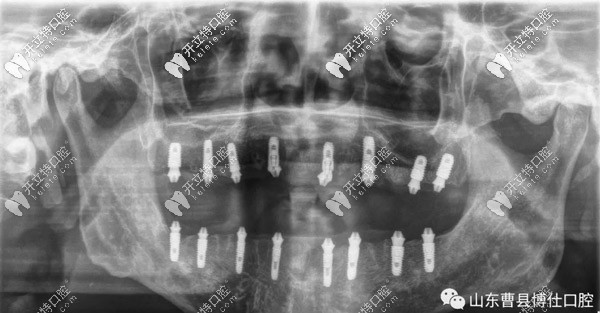

經(jīng)過(guò)一個(gè)半小時(shí)的手術(shù)時(shí)間,徐大爺上頜和下頜各植入8顆種植體,縫合傷口后,拍片顯示植入位置非常好。

之后,于院長(zhǎng)帶領(lǐng)博仕口腔的即刻修復(fù)團(tuán)隊(duì)開(kāi)始排牙、注膠、打磨、調(diào)咬合、拋光等,下午6點(diǎn)左右為徐大爺帶上了新牙。

通過(guò)拍片顯示,臨時(shí)牙和螺栓結(jié)合非常緊密,不需要調(diào)整,也經(jīng)過(guò)多次的反復(fù)咬合之后,并沒(méi)有不適的情況。